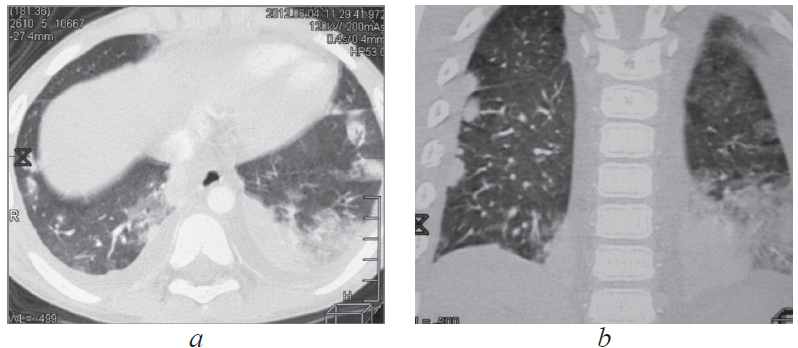

МСКТ грудной полости 04.06.2012 (рис. 2, а, b): «КТ-картина множественных двусторонних субплевральных инфильтратов легочной ткани, двусторонний гидроторакс. Выраженная гепатоспленомегалия. Лимфоузлы средостения и корней легких стабильны, по сравнению с МСКТ от 20.02.2012 с признаками кальцинации в прежнем объеме». Исследования на МБТ мокроты, промывных вод бронхов (микроскопия, полимеразная цепная реакция, посев) отрицательны».

Рис. 2. Пациент, 6 лет. Компьютерная томография грудной клетки от 04.06.2012: множественные двусторонние субплевральные инфильтраты в легких, двусторонний гидроторакс (а — аксиальная проекция, b — фронтальная проекция)

Fig. 2. Patient, 6 years old. Computed tomography of the chest, 04.06.2012: multiple bilateral subpleural infiltrates in the lungs, bilateral hydrothorax (а – axial projection, b – frontal projection)

После консультации фтизиатра специфический характер диссеминации в легких отвергнут. В связи с возможностью прогрессирования туберкулеза 07.06.2012 возобновлена противотуберкулезная терапия тремя противотуберкулезными препаратами — изониазидом, пиразинамидом, этамбутолом.